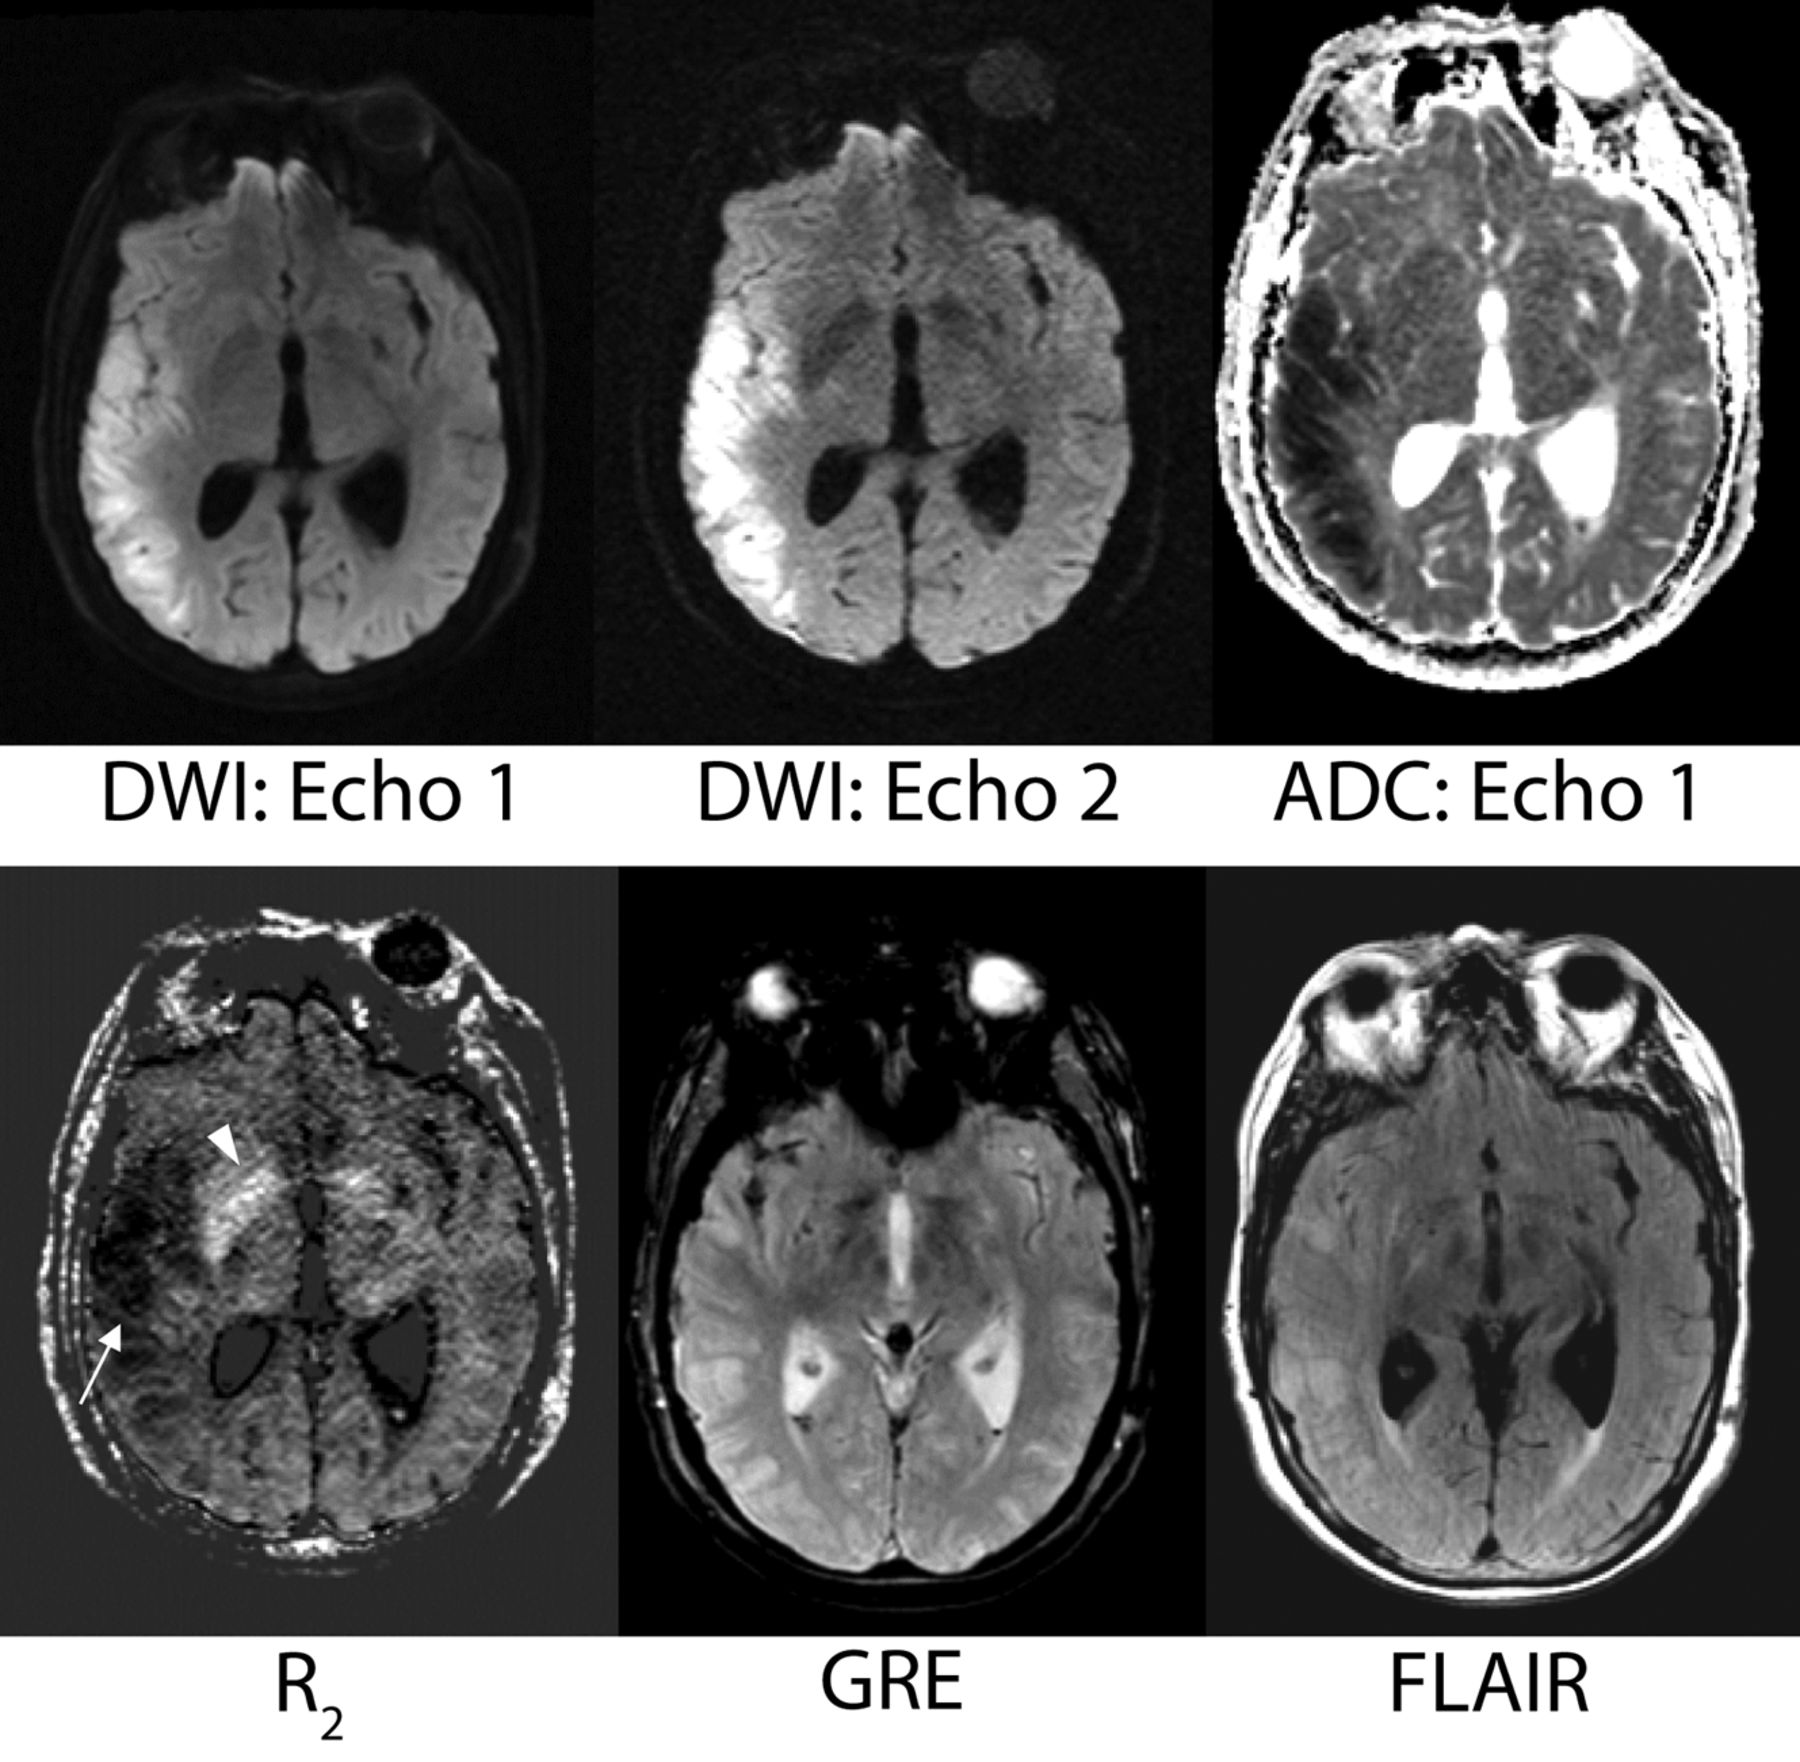

The R2 maps were deemed useful in several regards. Both acute and chronic infarcts demonstrated low R2 values that were readily apparent. Even small areas of ischemia were identified on the R2 maps. For instance, R2 maps frequently identified lesions presumed to represent chronic small-vessel ischemic disease in the periventricular and subcortical white matter, a finding typically identified on FLAIR and T2-weighted images. The R2 maps identified areas of subarachnoid, old cerebellar, and intraventricular hemorrhage (including some foci that were difficult to visualize on the GRE scan). Mineralization was depicted as regions of high R2 and was particularly notable in the basal ganglia (Fig 8).

A sample case showing the potential contribution of the R2 map. A 69-year-old female patient with vasospasm after subarachnoid hemorrhage. The low-R2 lesion is more conspicuous than the corresponding T2 hyperintensity on the FLAIR image. On the basis of DWI/ADC, this area represents acute right MCA territory infarction. The potential contribution of the R2 map with regard to timing of stroke and its evolution is unknown but prompts future investigation. The R2 map also shows more conspicuous mineralization in the basal ganglia than the gradient-recalled echo image (arrowhead).